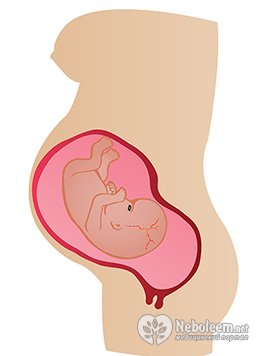

- 21-24 неделя – к концу шестого месяца вес плода 600-700 г, его длина 25-30 см. Формирование внутренних органов закончено, плод умеет производить дыхательные движения, но к внеутробной жизни он еще не готов. Крайне редки случаи выживания детей, которые рождаются в конце 6 месяца беременности;

- 25-28 неделя – плод продолжает расти и набирать вес, к концу седьмого месяца рост ребенка 30-35 см, его вес уже 1,0-1,5 кг, но хрящевая ткань еще не сформирована окончательно, поэтому ушные и носовые хрящи еще мягкие, а ногти не покрывают полностью ногтевые пластины. Сердце бьется с частотой 120-130 уд/мин, нервная система плода совершенствуется, начинается этап накапливания жировой клетчатки и окончательного формирования тела ребенка. Плод на 28 неделе считается недоношенным, но современные методы ухода и своевременная помощь делают шансы выживания для родившихся на седьмом месяце детей очень высокими;

29-32 неделя - вес 1,5-2,2 кг, рост 40-45 см, улучшена работоспособность внутренних органов, малыш открывает глаза. Расположен он уже головкой вниз и рождается вполне жизнеспособным, идет дальнейший набор веса и роста;

- 33-36 неделя – завершается внутриутробное развитие плода, он менее подвижен, из-за недостатка места для активного движения. Кожа малыша гладкая и розовая, хрящевая ткань ушей и носа уплотняется, ногтевые пластинки покрывают ногтевые лунки и выходят за окончания пальцев. Завершено формирование всех внутренних органов, они полноценно функционируют;

- 37-40 неделя – ребенок доношен, все органы и системы готовы к автономному функционированию, движения малыша замедленны в преддверии рождения. Кишечный тракт ребенка заполнен первородным калом, образовавшимся из всего, что он за это время проглотил – кожных чешуек, околоплодных вод, лануго, дефекация обычно происходит после рождения, но в некоторых случаях при стрессе частично кишечник малыша может быть опорожнен в околоплодные воды. Вследствие повышенного уровня эстрогена грудные железы девочек и мальчиков увеличены, припухлость спадает через 2-3 недели после рождения.